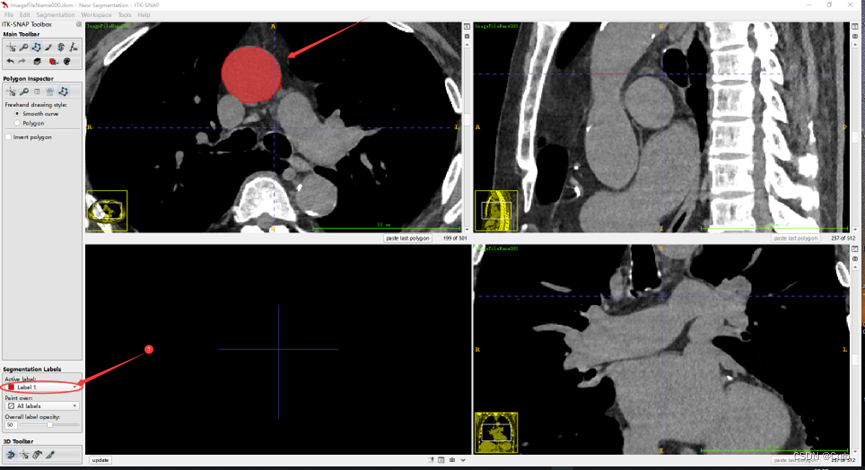

根据上图,选择好标注工具后,通过切换切片一张一张地进行标注(也可以通过滚动鼠标来切换),使用套索标注的例子(下面是放大之后的效果):

标注过程中,有两种方式,一种是通过长按鼠标左键进行标注;一种是通过不断单击鼠标左键进行标注。(具体感受一下就知道了)

对不同部位使用不同的标签,点击上图中的圈出位置,进行切换标签(颜色不同)。标注之后的效果如下:

为了方便标注,可以点击上图圈出的位置放大这个方向上的轴向图。效果如下